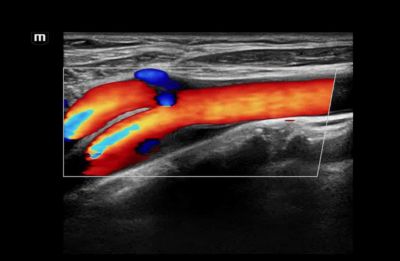

High-Res Flow (HR Flow)

This technology enhances the visualization of micro-vascular or complex flow patterns by applying processing algorithms within the system. HR Flow can be applied to Color and Power Doppler imaging modes.

HR Flow of Common Carotid Artery and Carotid Bifurcation

HR Flow of the Main Portal Vein and hepatic branches